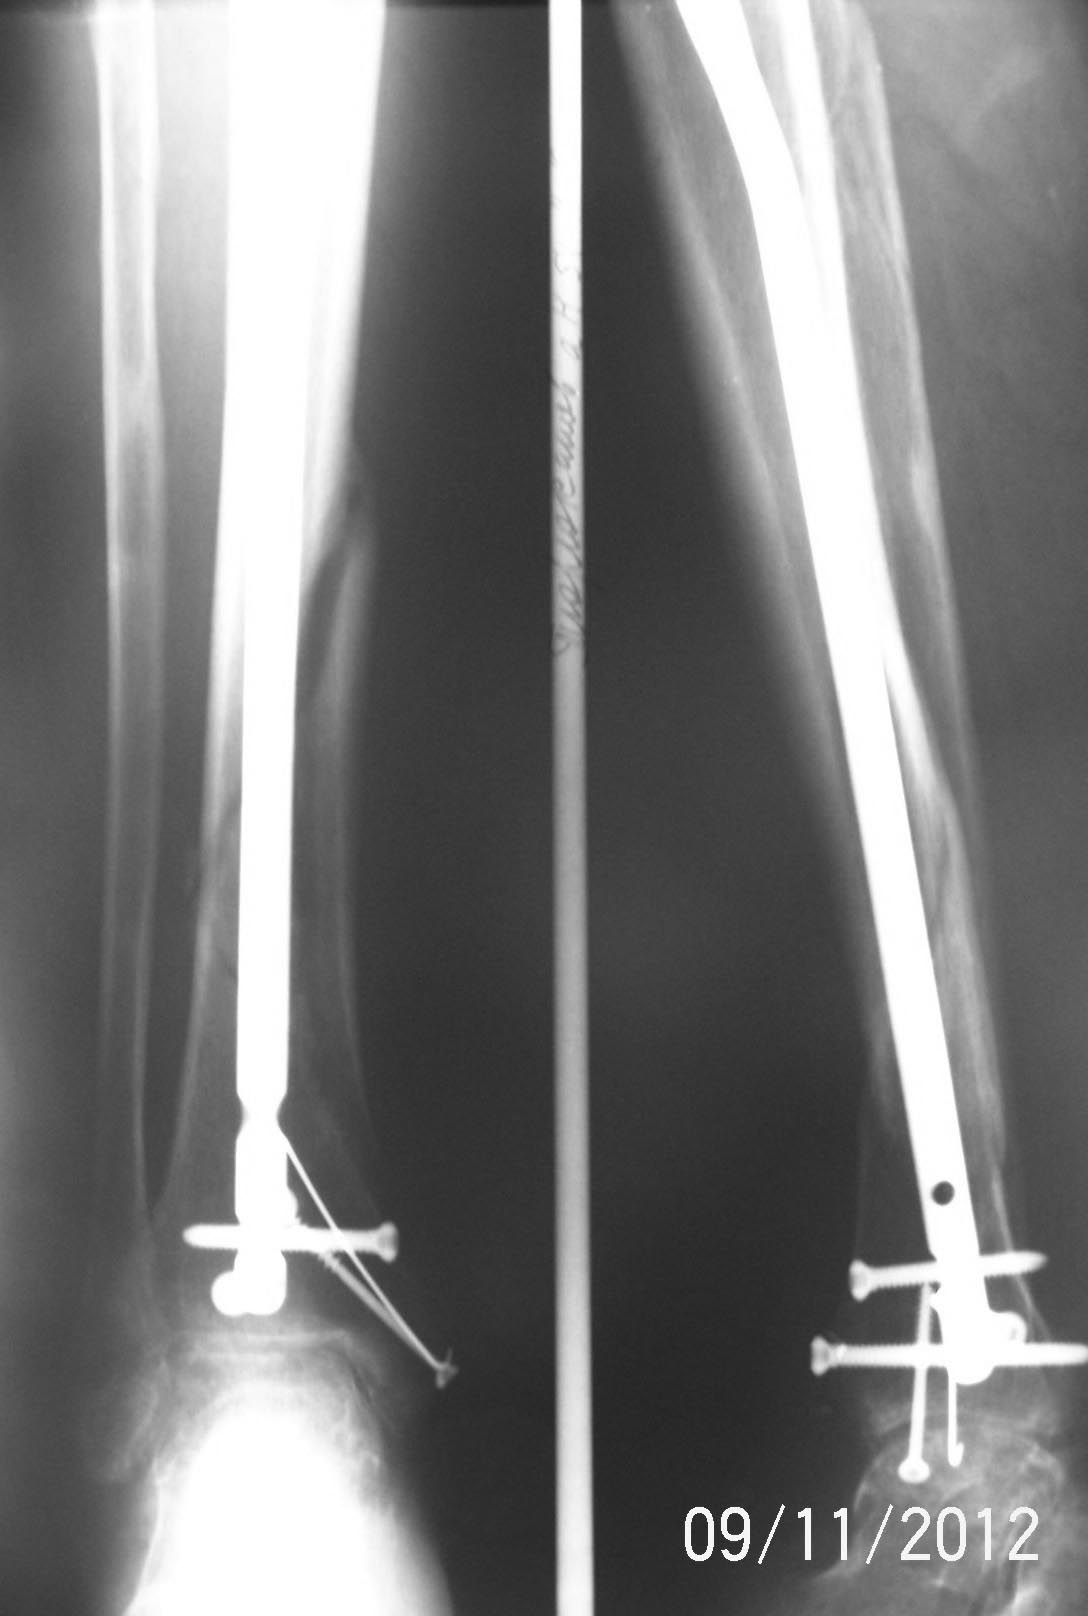

А можно увидеть самый свежий снимок в большем разрешении?

Последний.

Данный случай является одним из сложных, потому что спиральный фрагмент лежит отдельно, а основные части большеберцовой расположились ввиде заточенного карандаша. Динамизация при таких явлениях редко эффективна, и для ускорения процесса прибегают к замене гвоздя.

Снимки в двух проекциях недостаточны для оценки, надо добавить дополнительные косые 45 градусные снимки. Спиральная КТ лучше покажет окружность кости, но на последних снимках идет консолидация перелома, особенно наверху. Можно подождать и продолжать нагрузку!